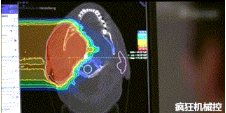

光柵掃描被集成到360°重離子治療一體機中,這種極其精確的照射方法以毫米為單位掃描腫瘤,可以保護健康組織且只治療腫瘤區域。

特別是腫瘤在高度輻射敏感位置或者諸如視神經附近的復雜位置,可以通過選擇最佳射束入射角來減小這些器官的損傷。